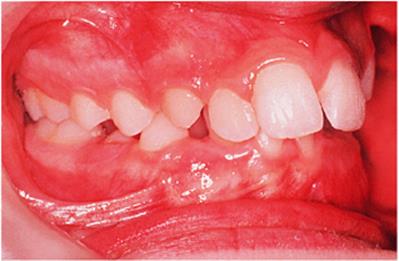

Before discussing functional appliances in detail, Fig. 18.1 gives an overview of this type of functional appliance in clinical use. This patient has a Class II division 1 malocclusion of the type for which functional appliances are very suitable, and for which they have been used for many years.

There are a number of important features to note which will be discussed further later in the chapter. First, the patient is still growing and the signs are that her pattern of facial growth is likely to be favourable. Although the skeletal pattern is Class II, the vertical relationships are close to average and the direction of mandibular growth is likely to be a mild forward rotation (see Chapter 4) which is favourable to the correction of a Class II malocclusion. Second, the soft tissue morphology is favourable despite the lips being incompetent, with the lower lip resting behind the upper incisors. The lower lip line is above the level of the upper incisal edges, and after the overjet has been reduced the lower lip will rest labially to the upper incisors, so helping to resist any tendency for relapse of the overjet. Third, the arches are well aligned — functional appliances have no mechanism for treating irregularities of alignment of the teeth.

Fig. 18.1. (a) This 12-year-old girl had a skeletal II facial pattern and average facial proportions. The lips were incompetent with the lower lip lying below the upper incisors at rest. (b), (c) She had a Class II division 1 malocclusion with an overjet of 10 mm, the overbite was increased and complete, and the molar relationship was Class II on both sides. (d), (e) The upper and lower arches were well aligned. (f) A functional appliance (an activator) was fitted. (g) The corrected occlusion with Class I incisor and molar relationships. (h) The patient's facial profile at the end of treatment.